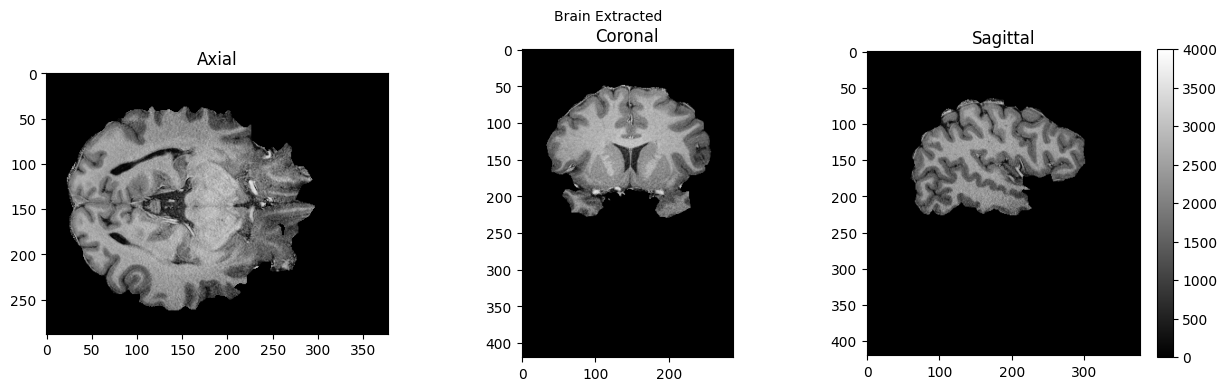

view_slices_3d(brain, slice_nbr=230, vmin=0, vmax=4000, title='Brain Extracted')